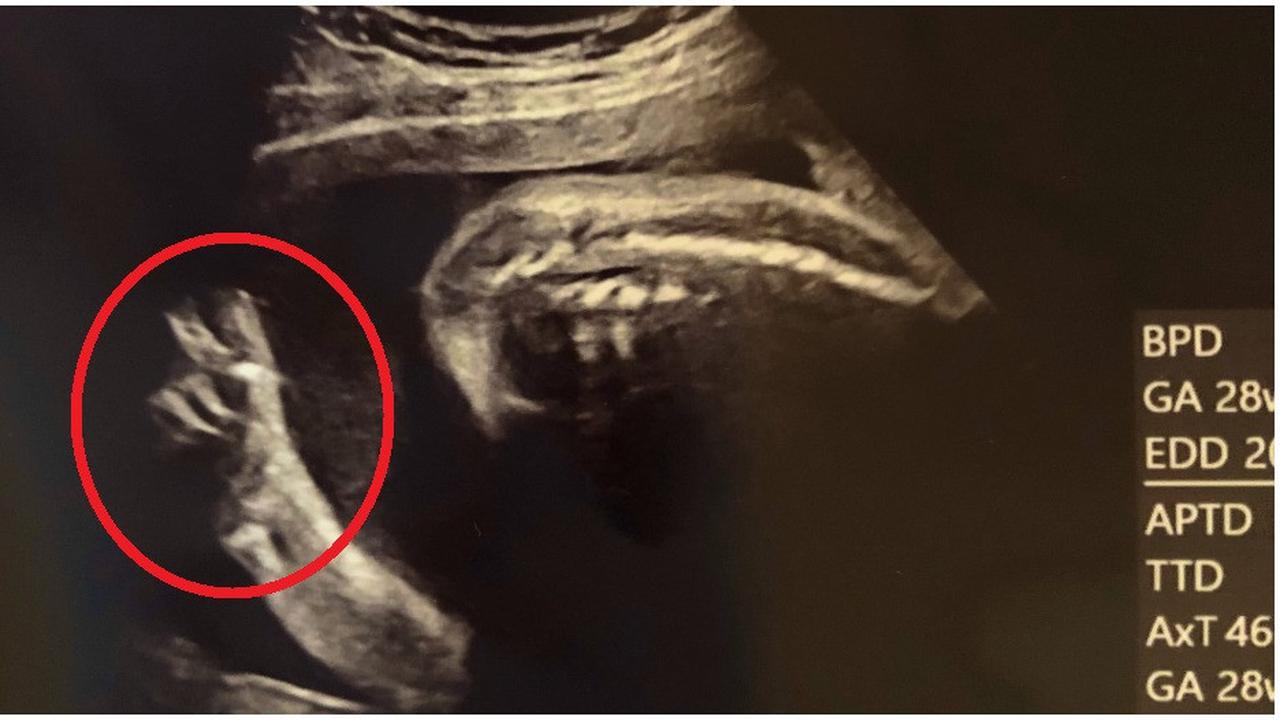

Itulah yang terjadi pada bayi tengah menjadi perbincangan viral ini. Saat menjalani USG saat hamil tujuh bulan, janin seorang ibu di Jepang, menunjukkan reaksi tak biasa.

“Bayi saya menunjukkan tanda perdamaian dari dalam. Dan sekarang saya terhibur,” kata ibu tersebut seperti melansir dari World of Buzz, Selasa (7/4/2020).

Momen tersebut pun dibagikan akun Twitter @madoka_people. Dalam unggahannya, akun tersebut membagikan sebuah foto hasil USG janin yang acungkan dua jari atau dikenal sebagai tanda damai.